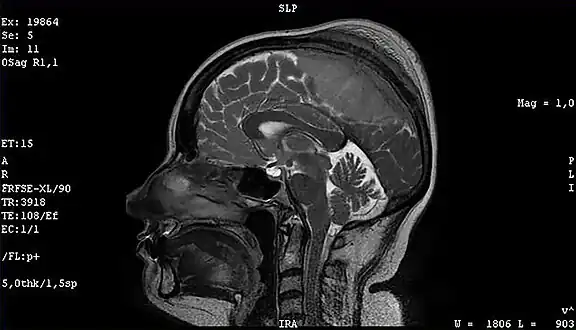

Image revealed a bilateral frontoparietal bone hyperostosis, particularly in the left side -

Meningioma of the middle third of the sagittal sinus with large hyperostosis